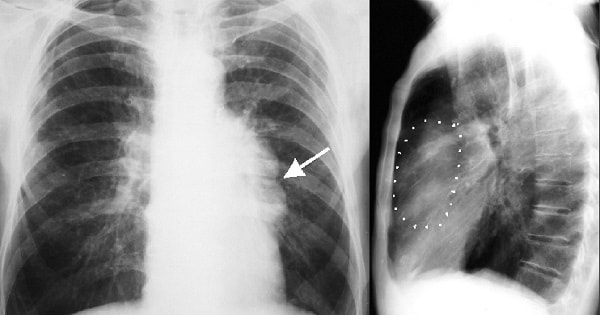

Hình ảnh chụp X-quang khối u trung thất

Nếu bạn có một khối u trung thất, bạn có thể không gặp bất kỳ triệu chứng gì. Các khối u thường hiện diện trên phim XQ ngực được chụp để chẩn đoán một tình trạng sức khoẻ khác.

- X-quang ngực

- Chụp CT ngực

- MRI ngực